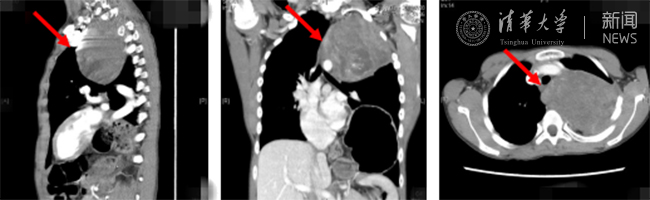

术中发现,肿瘤不仅占据胸腔内大部分空间,且与心脏、主动脉、腔静脉、下肺静脉等组织紧密粘连,一旦分离过程中损伤大血管致出血,受肿瘤阻挡的情况下,病人将很快因大出血死亡。在胸外科团队的协助下,手术团队顶住巨大压力,经过5小时的连续奋战,肿瘤被完整移除胸腔。在麻醉科团队的协助下,患者术中生命体征稳定,心率及血压控制良好,平稳地度过了手术麻醉期,术后返回重症监护病房。

术后复查影像,患者体内的肿瘤已被切除。